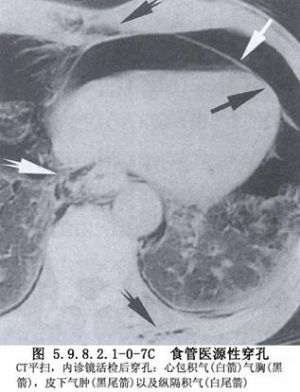

食管穿孔的早期診斷存在一定困難,在合併嚴重複雜損傷的情況下,其症狀及體徵往往被掩蓋。因此,在食管可能受到損傷的情況下,如果發現頸部、胸部皮下氣腫,應高度警惕食管穿孔的發生,此時X線檢查常有助於診斷。頸部食管穿孔,X線攝片早期即可發現頸部筋膜層有遊離氣體。若已形成膿腫則可出現局部緻密陰影,其中可有氣液麪。胸部食管穿孔,X線檢查可見縱隔積氣或縱隔影增寬,一側或雙側液氣胸。左側液氣胸常爲低位食管穿孔,右側液氣胸多爲中段食管穿孔。食管造影不僅可明確診斷,而且還能確定破裂部位、範圍及穿孔方向。胸腔穿刺抽出液呈酸性,pH<6,應考慮下段食管穿孔。口服亞甲藍溶液,胸腔穿刺抽出液呈藍色,可以確診食管穿孔(圖5.9.8.2.1-0-4~5.9.8.2.1-0-7)。